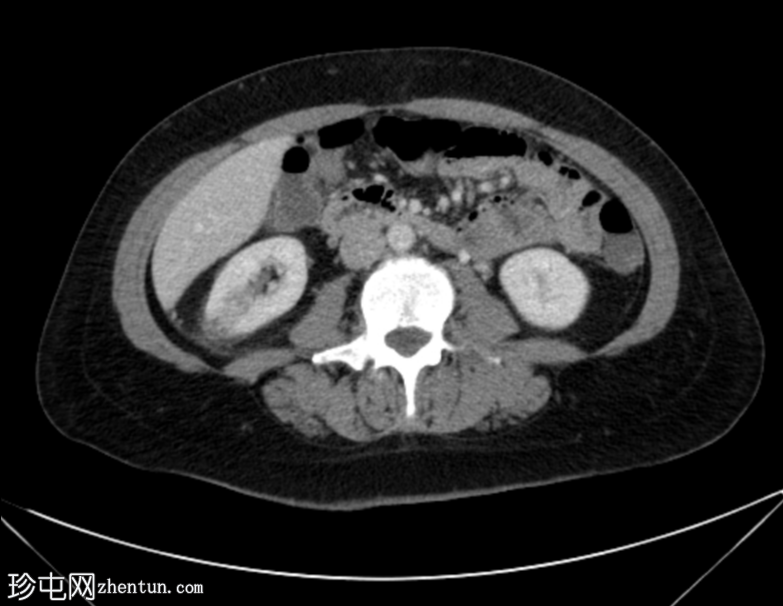

轴位增强扫描(门静脉期)

右肾轴位和冠状位图像均显示肾实质下部低强化区域,伴肾周脂肪间隙模糊,符合急性肾盂肾炎的

影像

学表现。

膀胱壁轻度环周增厚及强化,可能为轻度膀胱炎。